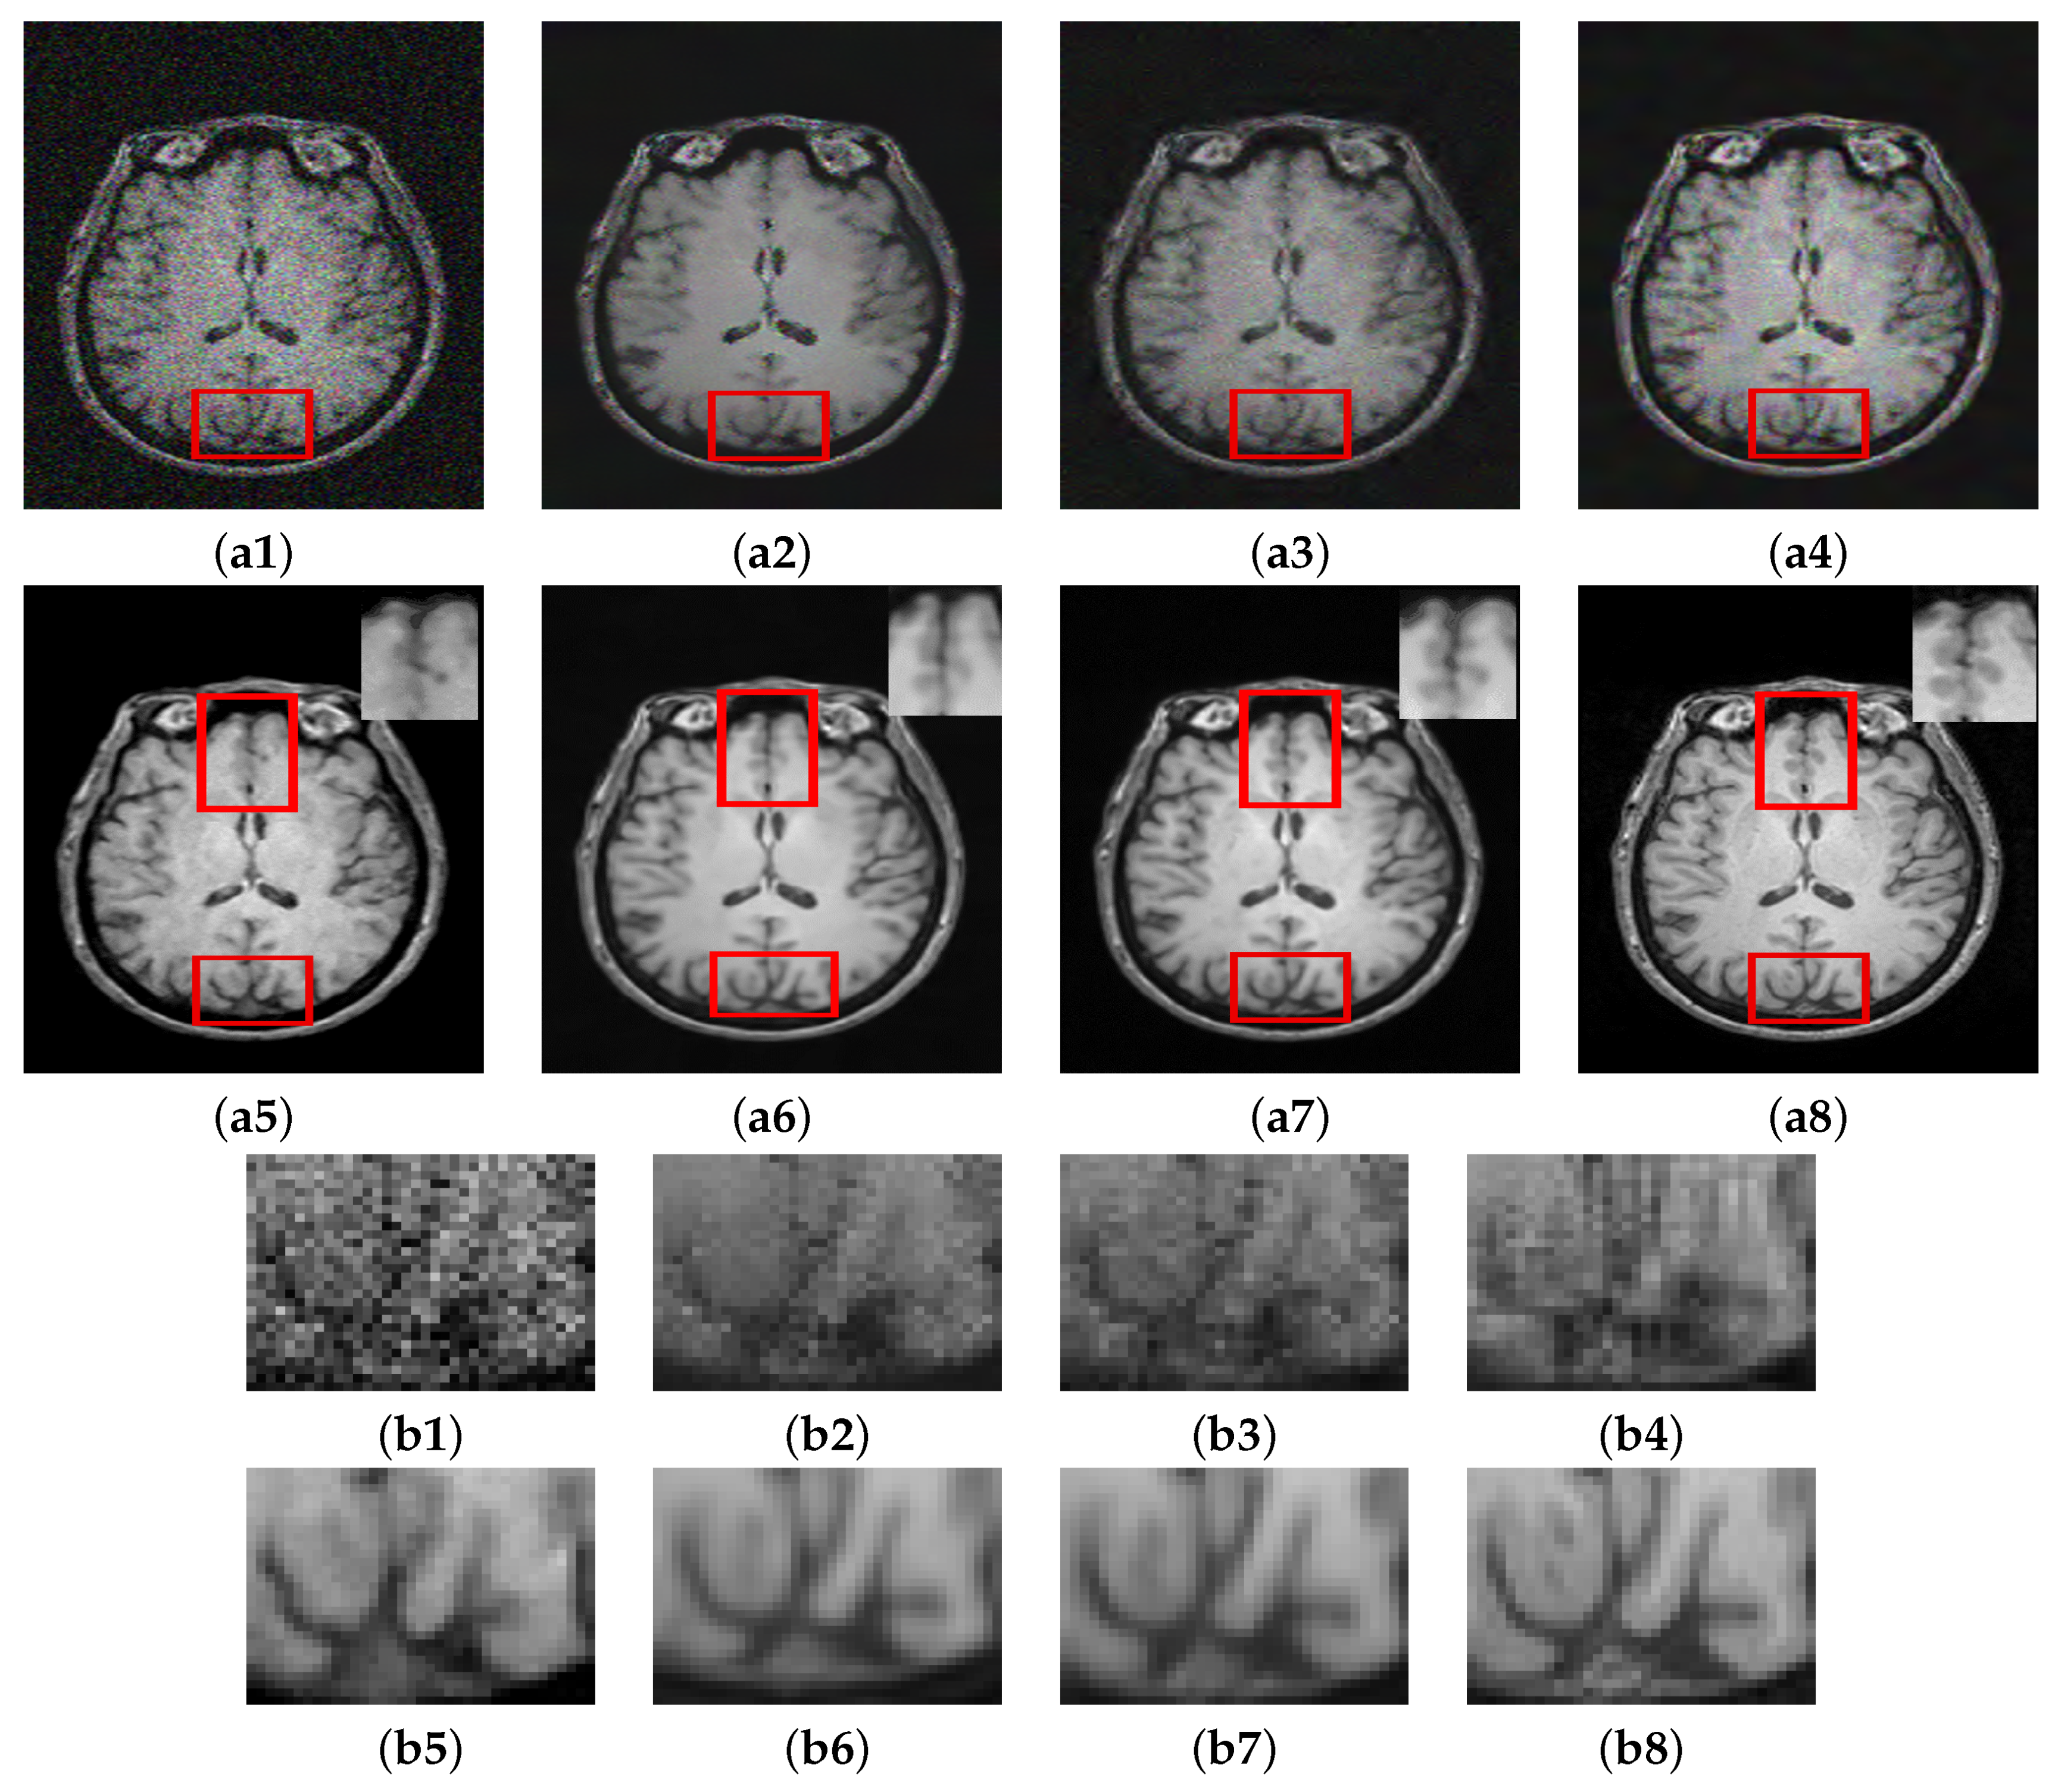

In this section, we summarize the discussion of our results. The results of Experiment I are shown in Figure 5, Figure 6 and Figure 7, where the denoising performance of the proposed method is shown in comparison with state-of-the-art denoising methods. In Figure 5, the input images were contaminated using 13% noise. All the images denoised using different approaches suppress noise to some extent; however, NLM [10] removes important structural details in the image and oversmoothes the contents of the denoised image during the restoration. Wavelet-based technique SURE [58] and BM3D [59] preserve the structural details; however, they do not eradicate noise to a reasonable extent. The deep learning methods clearly show better performance compared to the traditional methods, both in removing noise and maintaining the morphology of the image. Both MCDN [24] and FFD-Net [53] effectively remove the noise. Similarly, C M G D N e t also eradicates noise with reasonable preservation of the structural information. The enlarged ROIs are also shown in the figure for careful insight into the denoising performance of all the methods. Figure 6 shows the results of denoising applied on images contaminated with 8% noise. A similar trend can be observed in this case as well where the methods MCDN [24], FFD-Net [53], and C M G D N e t preserve important structures in the denoised images. However, NLM [10] produces over-smoothing effects. The performance was quantitatively evaluated using PSNR, SSIM, and FSIM. BM3D [59] works better compared to NLM and SURE [58]; this claim is also supported by the higher PSNR value in Table 2. The performance of FFD-Net [53] and MCDN is very similar when quantitatively evaluated. However, C M G D N e t performs best among all the techniques evaluated.

Figure 5. Comparison of proposed method with state-of-the-art denoising methods: (a1) Noisy. (a2) NLM [10]. (a3) SURE [58]. (a4) BM3D [59]. (a5) MCDN [24]. (a6) FFD-Net [53]. (a7) C M G D N e t s g . (a8) GT, Corresponding enlarged regions of the denoised images: (b1) Noisy. (b2) NLM [10]. (b3) SURE [58]. (b4) BM3D [59]. (b5) MCDN [24]. (b6) FFD-Net [53]. (b7) C M G D N e t s g . (b8) GT.